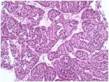

Der er mange forskellige former for nyrekræft, som ser forskellige ud i mikroskopet, og som opfører sig forskelligt i nyrerne. Nogle typer er mere aggressive end andre, og valg af behandling samt udsigten til at blive helbredt afhænger blandt andet af, hvilken type nyrekræft man har. Nyrekræft inddeles i følgende undertyper, som alle har en evne til at udvikle sig til mere aggressive former:

Fuhrman grad: Inddeling efter Fuhrman-skalen tager udgangspunkt i, hvordan cellerne i en vævsprøve ser ud. Kræftceller ser nemlig anderledes ud end normale raske celler. Man ser på to ting: kernerne i cellerne og kernelegemerne (nukleoler), der sidder inde i cellekernerne. Alt efter hvor anderledes (atypiske) cellerne er, inddeles de grad 1 til grad 4, hvor grad 1 er mindst ondartet. Man bruger Fuhrman-graden til at vurdere sygdommens alvor.